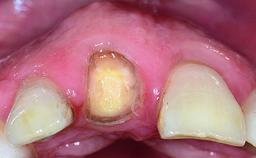

Replacement of a Compromised Upper Right Central Incisor: Hard- and Soft-tissue Augmentation, Late Placement of an RC Bone Level Implant

A 36-year-old male patient with a compromised maxillary central incisor was referred by his general dentist for consultation. The patient’s chief complaints were the gradual debonding of a temporary crown on the right central incisor and unsatisfactory esthetics due to an increasing diastema between the right central and lateral incisors. The patient reported a traumatic event some years previously, when a crown had been placed after root-canal treatment. The referring dentist wanted to provide a new crown restoration, but was concerned about the condition of the residual root. Anamnesis was negative for any other dental or periodontal pathology in the remaining dentition. The patient reported taking no medications: He was a smoker (10 to 15 cigs/day) and had realistic esthetic expectations.